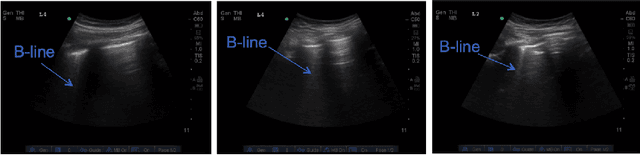

Abstract:Lung ultrasound (LUS) imaging is becoming popular in the intensive care units (ICU) for assessing lung abnormalities such as the appearance of B-line artefacts as a result of severe dengue. These artefacts appear in the LUS images and disappear quickly, making their manual detection very challenging. They also extend radially following the propagation of the sound waves. As a result, we hypothesize that a polar representation may be more adequate for automatic image analysis of these images. This paper presents an attention-based Convolutional+LSTM model to automatically detect B-lines in LUS videos, comparing performance when image data is taken in Cartesian and polar representations. Results indicate that the proposed framework with polar representation achieves competitive performance compared to the Cartesian representation for B-line classification and that attention mechanism can provide better localization.

Abstract:Lung ultrasound (LUS) imaging is used to assess lung abnormalities, including the presence of B-line artefacts due to fluid leakage into the lungs caused by a variety of diseases. However, manual detection of these artefacts is challenging. In this paper, we propose a novel methodology to automatically detect and localize B-lines in LUS videos using deep neural networks trained with weak labels. To this end, we combine a convolutional neural network (CNN) with a long short-term memory (LSTM) network and a temporal attention mechanism. Four different models are compared using data from 60 patients. Results show that our best model can determine whether one-second clips contain B-lines or not with an F1 score of 0.81, and extracts a representative frame with B-lines with an accuracy of 87.5%.